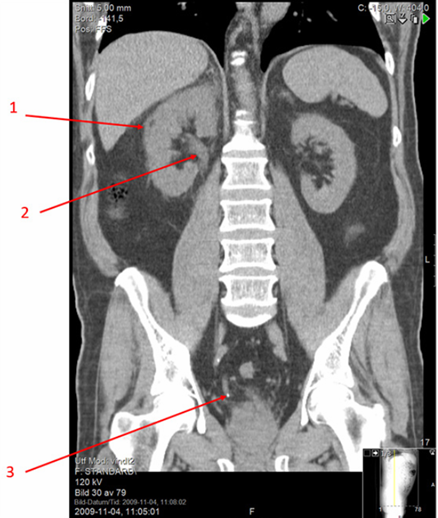

Vad ser du på bilden?